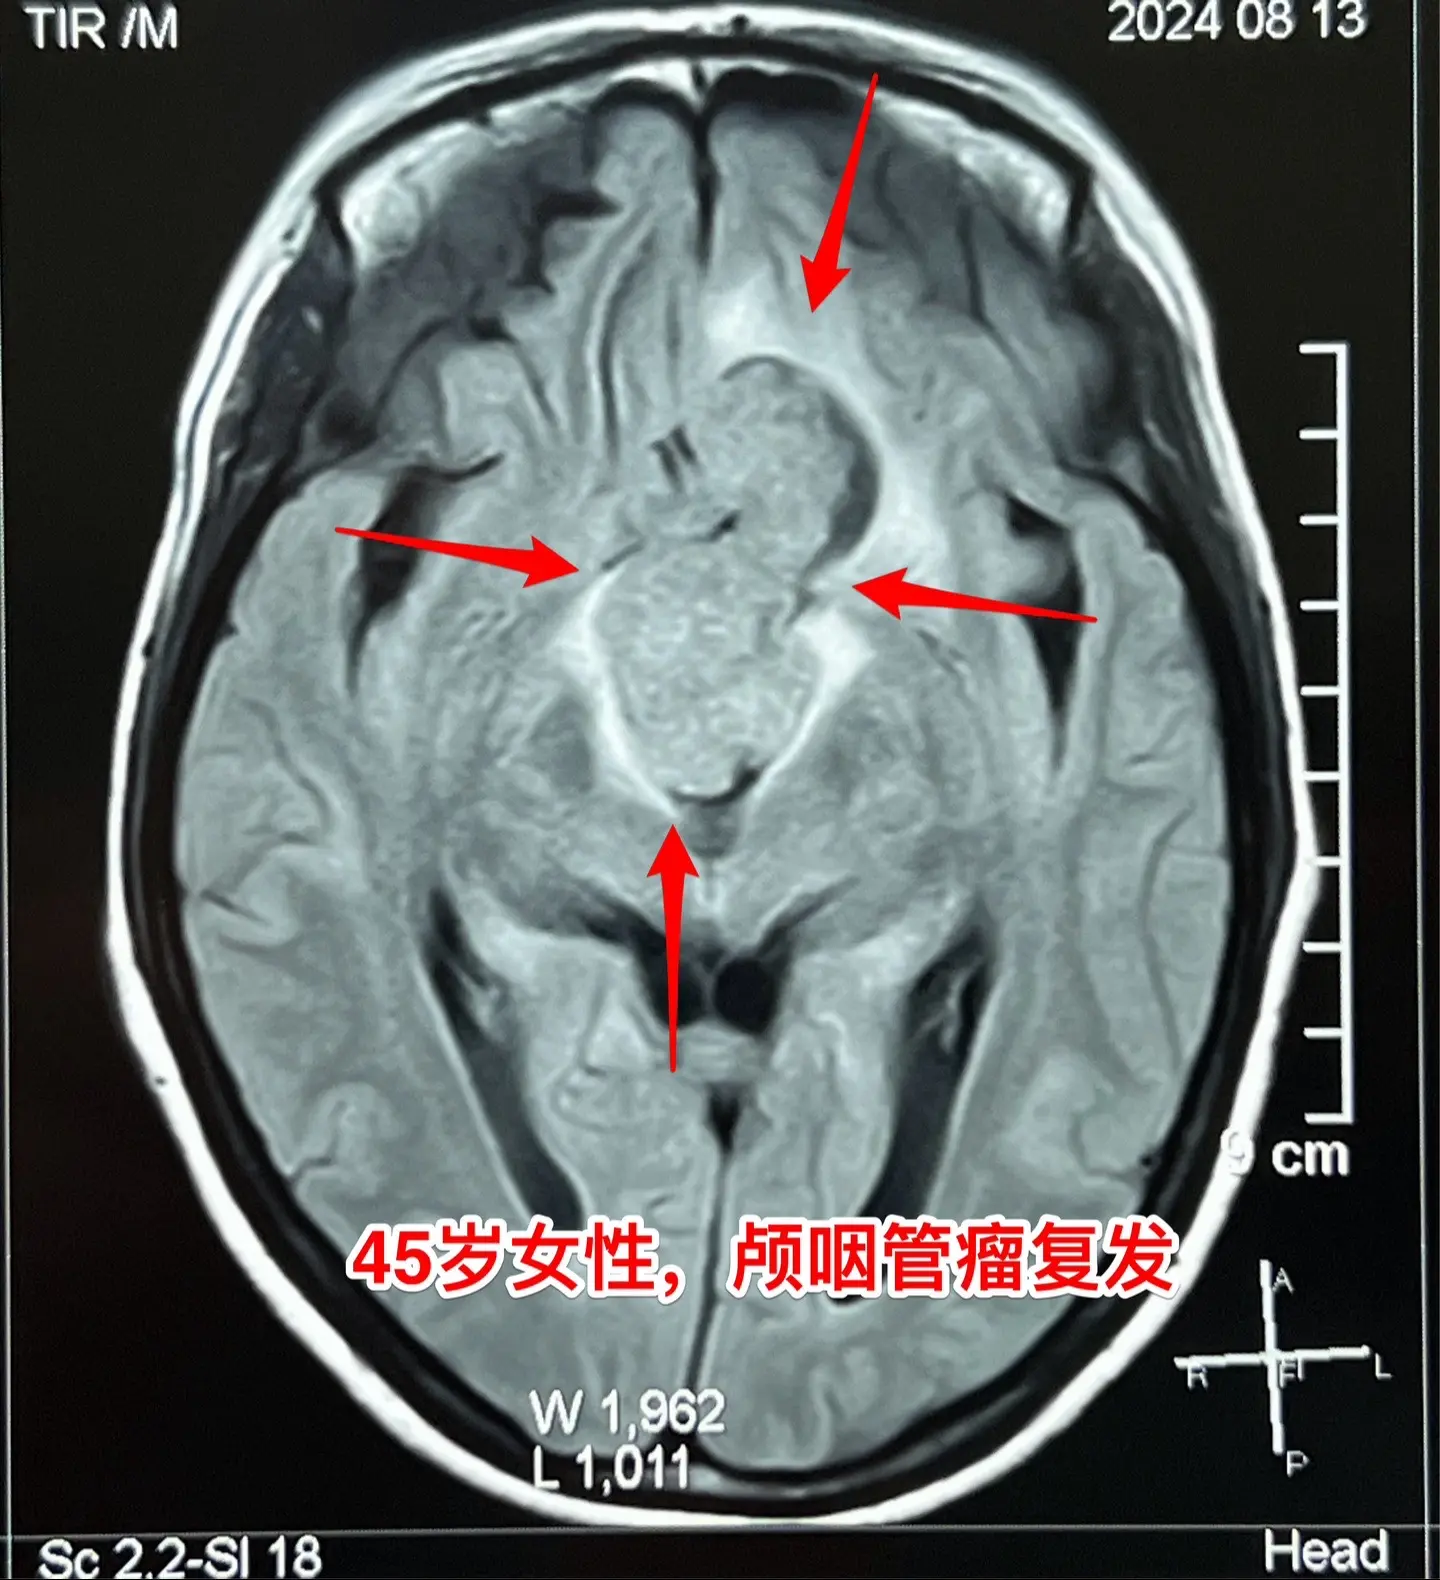

巨大的颅咽管瘤。45岁浙江女性,在外院作了颅咽管瘤手术不到一年,作磁共振显示肿瘤复发,而且体积巨大。 病人视力很差,记忆力也差,精神不好。 这么大的颅咽管瘤一般是需要作手术的。显而易见是这样的手术是很有难度的,很考验医生的技术和能力! 从影像学资料可以看出,这是乳头型颅咽管瘤。如果害怕作手术,对于运气好、经济状况好的病人,也可以试一试靶向药,也许有效。 这个病人选择了作手术!8月16日我们经过九个小时的紧张奋战,将肿瘤完全切除了。手术后CT结果很好。